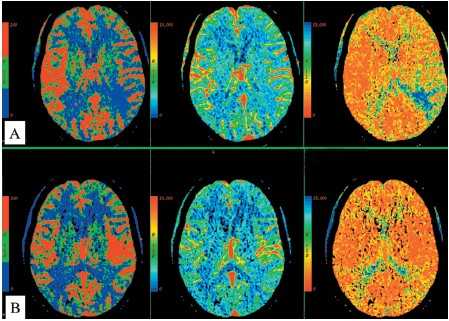

Перфузионно-взвешенные МРТ во многом аналогичны перфузионным изображениям при КТ. Т2-градиентные МРТ отражают магнитную чувствительность. Яркий сигнал на ДВИ МРТ коррелирует со снижением кровотока на перфузионно-взвешенных МРТ головного мозга.

МРТ головного мозга. Перфузионно-взвешенная МРТ. Снижение кровотока в левой лобной доле.

МРТ головного мозга. Сопоставление диффузионно-взвешенной и перфузионно-взвешенной МРТ.